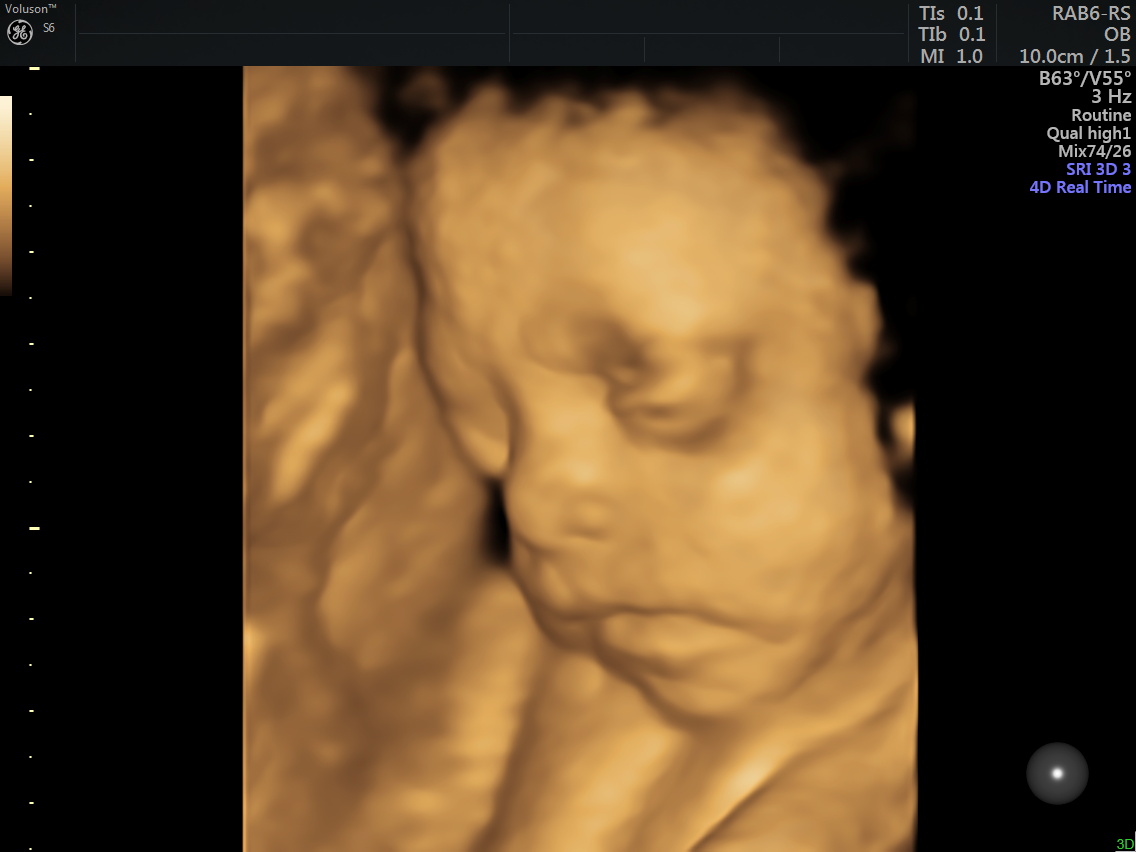

4D (dört boyutlu), Renkli, Ayrıntılı Gebelik Ultrasonu

4 boyutlu renkli ultrason ve 3 boyutlu ultrason aslında aynı anlama gelmemesine rağmen halk arasında , ayrıntılı ultrason, detaylı ultrason , ileri düzey ultrason, anomali ultrasonu , 2. basamak ultrason, ikinci düzey ultrason, renkli ultrason , büyük ultrason , genetik ultrason ile aynı anlamda kullanılmaktadır.

Anne adayı 4D Renkli Ultrason Sayesinde Bebeğine Daha Kolay Bağlanabilir.

4 boyutlu renkli ultrason cihazı ile çok erken dönemde cinsiyet, yarık dudak, yarık damak, eksik parmak, beyin ve omurilikten kaynaklanan rahatsızlıkların erken tanısı konulabiliyor.